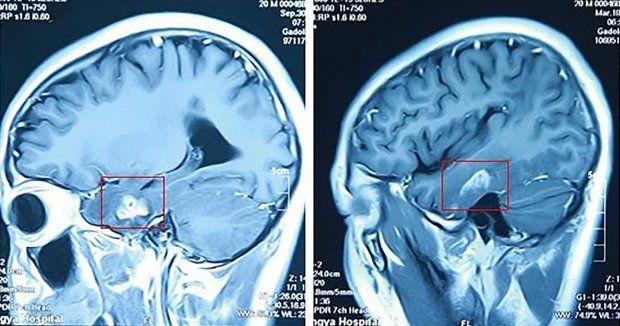

gif_animation 中国にて、カエルを食べたあと「頭痛がし始めた」という男性のレントゲン写真を撮った結果、脳内に長さ10cmの寄生虫が侵入していたというニュース。男性はカエルを食べようと皮を剥いだ際、誤ってナイフで手を切ってしまったといい、おそらくはその傷口から寄生虫が侵入したと思われる。その後、手術により寄生虫は無事除去された。